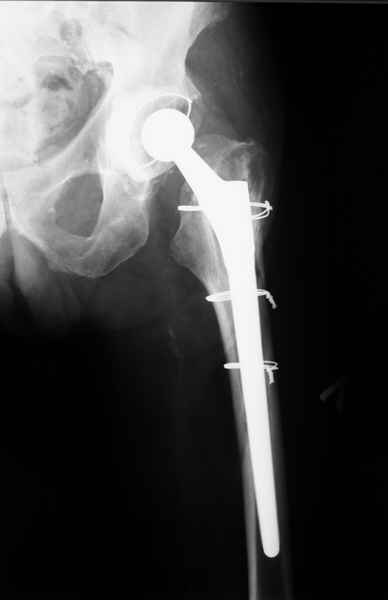

Произведено закрытое удлинение ножки эндопротеза с помощью ретроградного интрамедуллярного стержня. Продолжительность операции 3 часа. Два из них закрытое восстановление длины бедра диистрактором

таз-бедро.

А нельзя ли увидеть и профиль бедра на всем протяжении, т.е. и весь протез, и весь стержень? И фас бы с коленом.

новые снимки

Пациента удалось осмотреть недавно. Достигнутый результат сохраняется. Перелом бедра сросся. Конечность опорная и безболезненная, ходит без трости. Ножка, похоже, реинтегрировалась, как и надеялись. Снимки и фото в приложении. Комментарии приветствуются.

Надо ли что-то делать дальше, как полагаете? Убрать винты? Убрать "удлинитель ножки"? Или оставить все, как есть? Спасибо заранее.